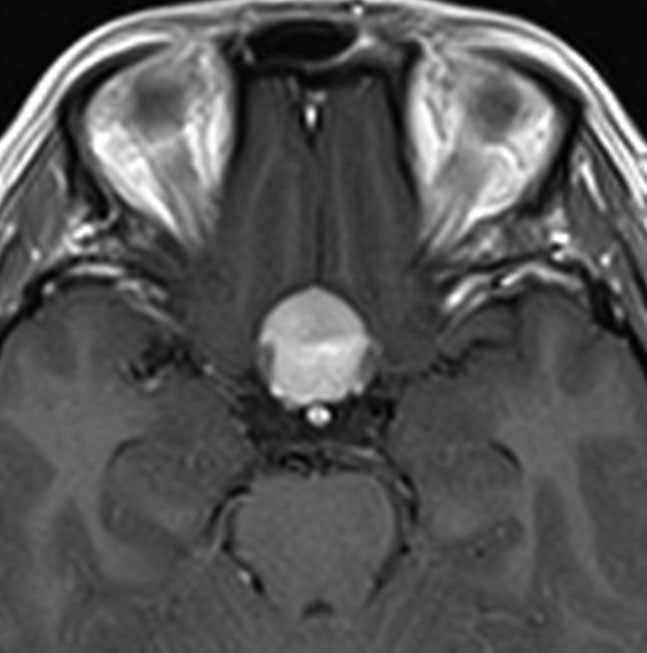

大後頭孔(大孔)髄膜腫 foramen magnum meningioma)

この腫瘍はfarlateral approachなどの頭蓋底手術をしなくても,外側後頭窩開頭で全摘出できます。要領は,S状静脈洞の下端の周囲骨を削除することです。大後頭孔髄膜種は延髄を圧迫するので巨大なものはありません。出血のコントロールや延髄からの剥離は比較的容易なものが多いでしょう。舌咽神経と迷走神経損傷を避けることが重点となります。

迷走神経と舌咽神経は機能温存できました。舌下神経が腫瘍の表面に薄く広がり剥がすことができずに半分以上を切断しています。でも片側舌下神経麻痺では日常生活に困ることはあまりありません。